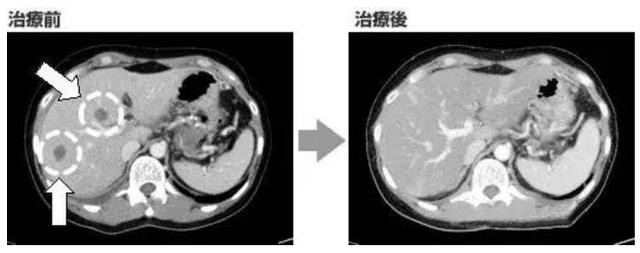

2016年2月被诊断为胰腺癌晚期(胰腺尾),转移到肝脏,肺,胸膜,并被诊断同时患有癌性腹膜炎(胸壁,肺部有多处结节)。

因为太晚期了,郑女士根本没有什么好的治疗选择,手术不能做,放疗也不能照射遍布全身的肿瘤病灶,唯一的选择就是NK细胞免疫治疗。一个周期结束后,效果并不理想,CA19-9从257,531,升至318,417。在医生的建议下,做了全基因组测序,结果没有任何有意义的突变,郑女士面临的似乎只剩下绝路一条,医生说她最多还有三个月到半年。

没想到的是,治疗十分顺利,第一次治疗结束后,CA19-9直接降到7355。第四次高度活化NK细胞治疗后,已降至141。2016年底,复查的CT图像显示,肝部和肺支气管淋巴结等转移病灶已消失。原发部位的胰腺癌也缩小了大半。现在,郑女士仍然在接受治疗,并且重新联合化疗增强杀癌威力,在医院继续随访的同时,被告知郑女士重返职场,只是郑女士转为处理集团行政上的决策,再也不会透支自己的身体。